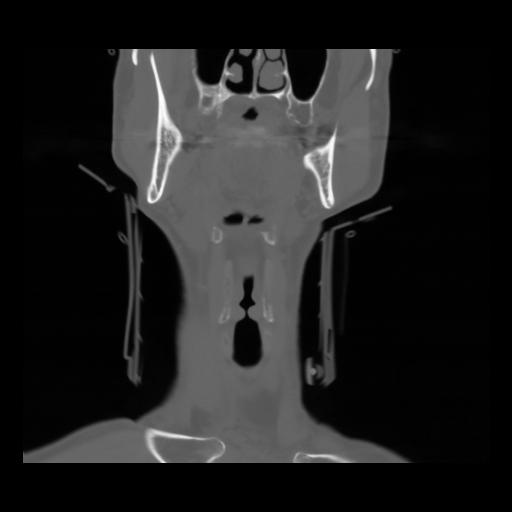

13 P.BLANDAS,,Coronal,2.000,P.BLANDAS,Coronal,